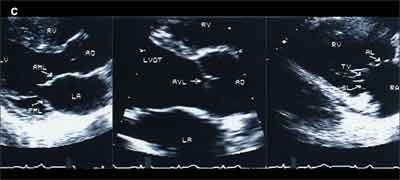

An echocardiographic study showed abnormally thickened and rigid mitral, aortic, and deformed tricuspid leaflets (A). Color flow Doppler images showed abnormal regurgitation at all 3 valves without stenosis (B). Peak right ventricular pressure was 26 mm Hg. Left ventricular function was normal (estimated ejection fraction of 60% to 65%). Because no previous echocardiogram-obtained before the patient started taking the drugs-was available, images of normal cardiac valves are shown for comparison (C).